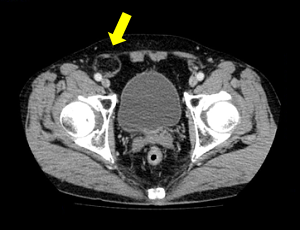

���`�ɂP�Omm�̌��������ē����������Ȃ��̒��ɑ}�����A���ǂɊJ�������i�w���j�A��j���m�F���A���b�V���V�[�g�����ɂ��Ăĕ����܂��B